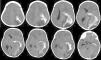

Teratoma is a common form of germ cell tumors composed of multiple tissues foreign to the site in which arise with a histological representation of all three germ cell layers. Intracranial teratomas are very rare. In this study, we report three cases of intracranial teratomas with an interesting clinical course, neuroradiology, and outcome. In addition, we review the literature and convey important messages to the neuroscience community regarding issues related to the management of these rare tumors. The present cases are interesting examples of intracranial teratoma in terms of location of the tumor and neuroimaging findings. Delay in surgical intervention may complicate the course of the disease with progressive enlargement of tumors and development of complication including hydrocephalus. Using endoscopic surgical techniques may emerge as the preferred intervention option as compared to other traditional methods. We recommend the establishment of a national and international registry for intracranial tumors.